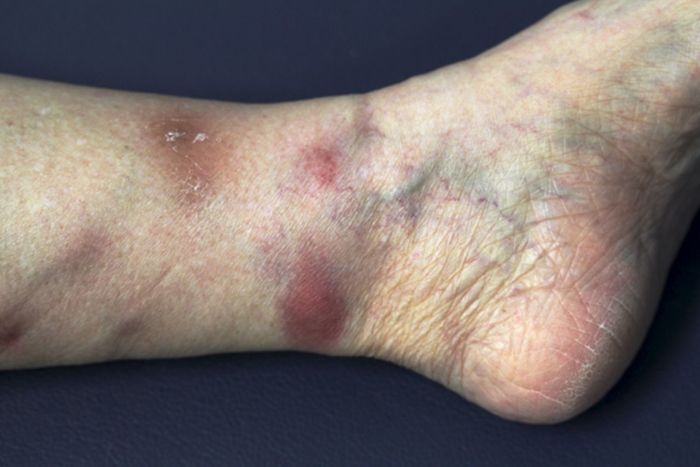

Image Description

An image of a lobular panniculitis lesion would typically show multiple, firm, subcutaneous nodules, often with a slightly erythematous appearance. The lesions can vary significantly in size and distribution across the body. The skin around the nodules might be slightly discolored. The nodules may be tender or painful to the touch.